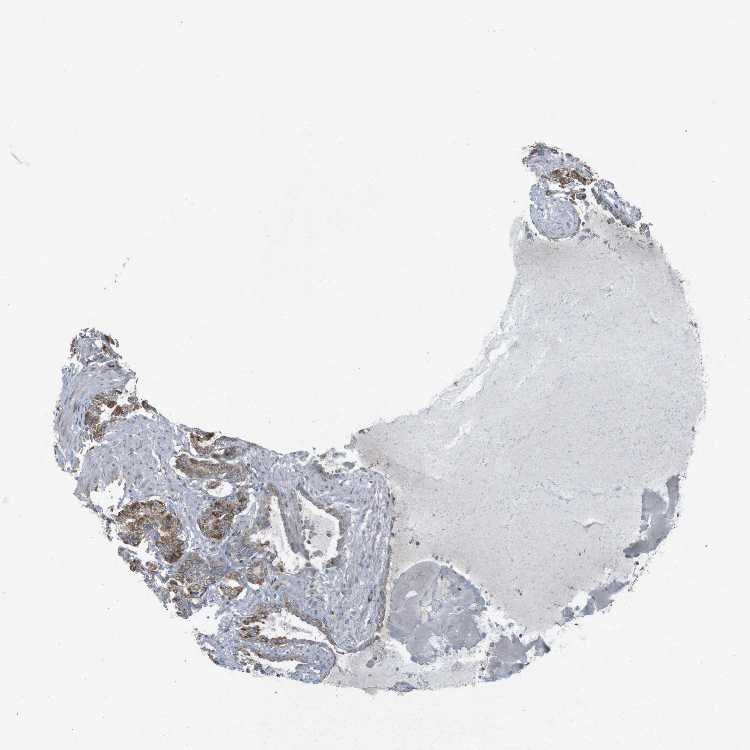

SEMINAL VESICLE - Antibody stainingi

Antibody staining in the annotated cell types in the current human tissue is reported as not detected, low, medium, or high, based on conventional immunohistochemistry profiling in selected tissues. This score is based on the combination of the staining intensity and fraction of stained cells.

Each image is clickable and will lead to virtual microscopy that enables deeper exploration of all samples and also displays staining intensity scores, fraction scores and subcellular localization as well as patient and tissue information for each sample.

Antibody HPA028760Antibody CAB015158

Glandular cells MediumMedium